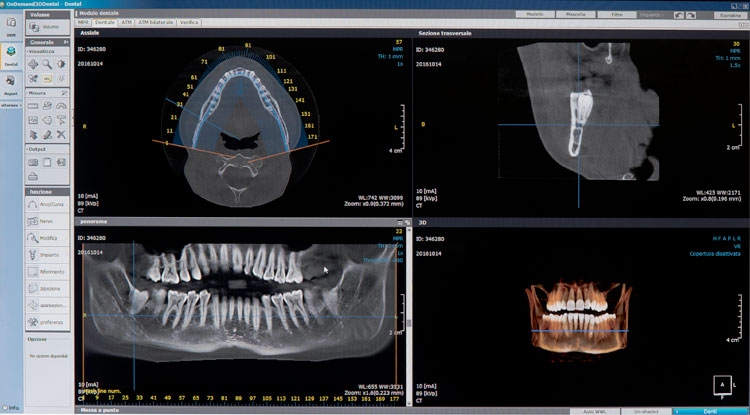

Lo Studio è dotato di un moderno sistema di radiologia digitale NewTom 3D TC di ultima generazione Cone Beam che in soli 15/20 minuti esegue un completo esame tridimensionale. Progettato dai pionieri del CBCT 3D in ambito dento-maxillofacciale, NewTom offre le migliori performance e la straordinaria qualità dell’imaging 3D. Direttamente nel vostro studio di fiducia, è possibile eseguire esami radiografici completi del complesso maxillofacciale con tecnologia UHD digital di ultima generazione a ridotta emissione di radiazioni per esposizione.

Sezioni Tomografiche (TC/Tac) e Ricostruzioni 3D dei mascellari Ortopantomografia delle arcate dentarie a bassa emissione di radiazioni X Ortopantomografia delle arcate specifica per uso pediatrico Rx Stratigrafia dei condili mandibolari compresa ATM Emimandibola dx/sx Adatta per adulti e bambini, veloce e indolore, consente di ottenere in tempo reale i referti necessari per le diagnosi e la pianificazione delle cure. Lo specialista garantisce le stesse tariffe applicate presso le strutture sanitarie specializzate esterne pur offrendo un prodotto avanzato, confortevole e sicuro.